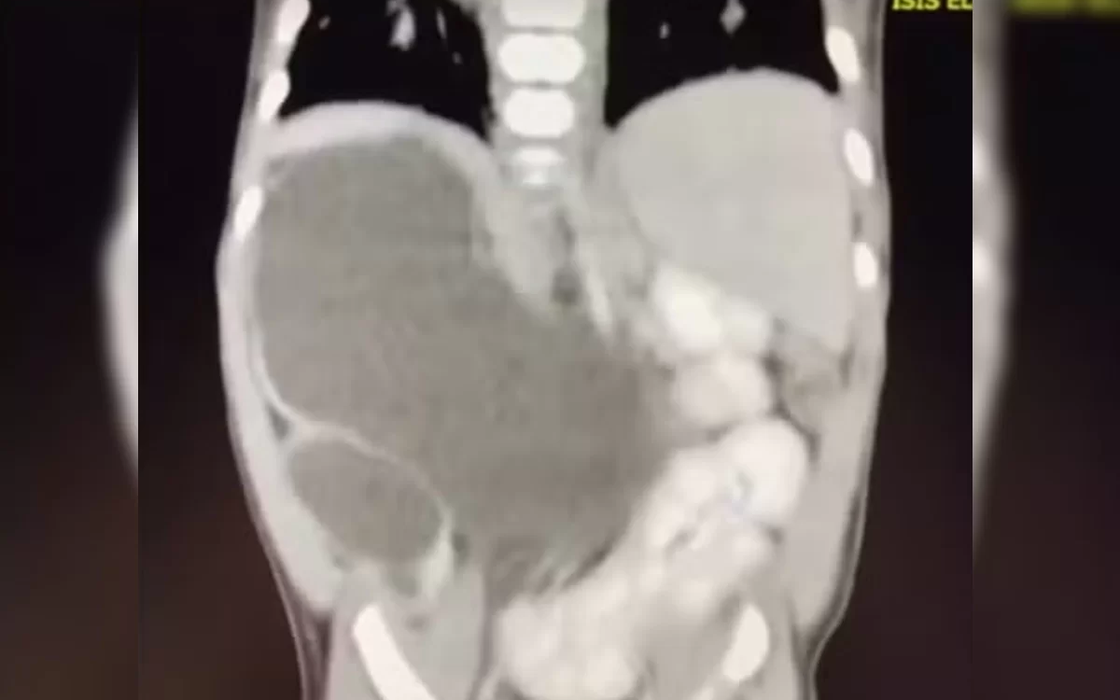

Menina nasce com quatro rins e está entre 100 casos no mundo

Incluída nos casos raríssimos da medicina, uma menina nasceu com quatro rins. Hoje com 1 ano e 1 mês, a pequena Isis Eloah Ferreira Alves está entre os cerca de 100 casos da medicina documentados na literatura mundial. O caso, publicado pelo G1, é é conhecido na medicina como “rins supranumerários” e demanda acompanhamento.

Aos 5 meses, quando houve a necessidade de Isis passar por uma cirurgia, os médicos confirmaram que ela tinha nascido com quatro rins. Como Formosa fica a cerca de 80 quilômetros do Distrito Federal, a menina hoje é tratada no Hospital da Criança de Brasília (HCB).